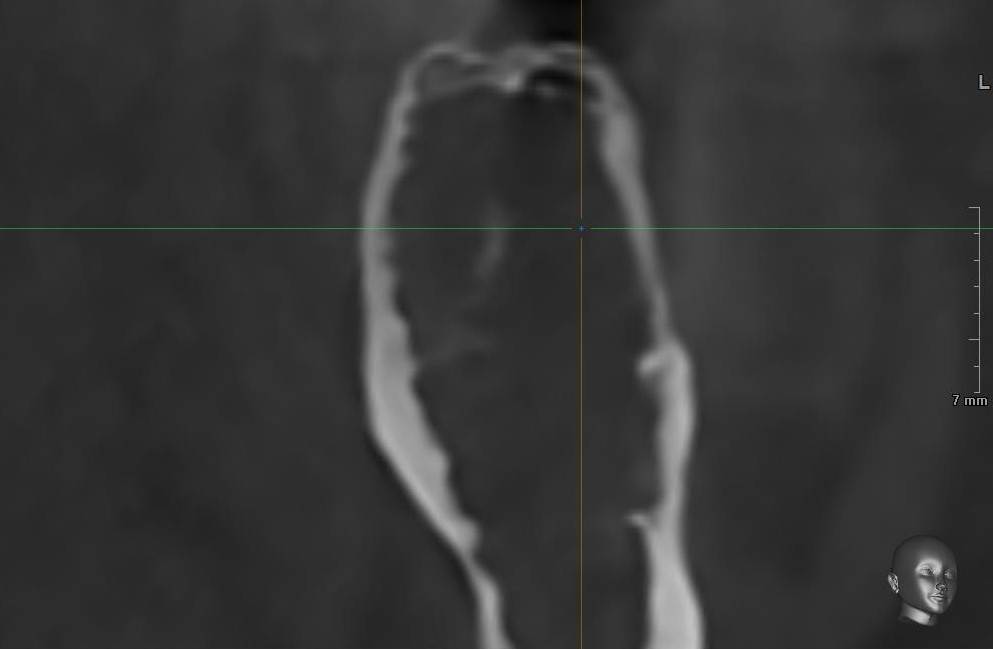

Aquarius Опубликовано 19 часов назад Поделиться Опубликовано 19 часов назад Здравствуйте, коллеги! Рад всех видеть - читать! Надеюсь никого не призвали-забрали)) Возник вопрос . В практике нередко бывают ситуации, которые немного выходят за рамки , скажем так , обычных кейсов. К примеру - как вы поступаете в случае имплантации в зонах очень мягкой кости, в нетипичных для этого анатомических областях ? К примеру не бугор в/ч, а тело нижней челюсти у соматически здоровой, не курящей пациентки средних лет? Имплант JD . Недопреп почти в 2 раза по диаметру - имплант проваливается в тело и в сторону. Собственно вопрос - подключаете фарму? Якобы спорный Остеогенон? Вит Д3? Или как то по другому выходите из ситуации? Спасибо Ссылка на комментарий

Aquarius Опубликовано 19 часов назад Автор Поделиться Опубликовано 19 часов назад Логика подсказывает - если бигфарма и тем более сообщество коллег не всегда разделяют мнение об успехах остеотропной терапии, то остается только вариант местной оссеоденсификации . Типа Денса боров и так далее? Ссылка на комментарий